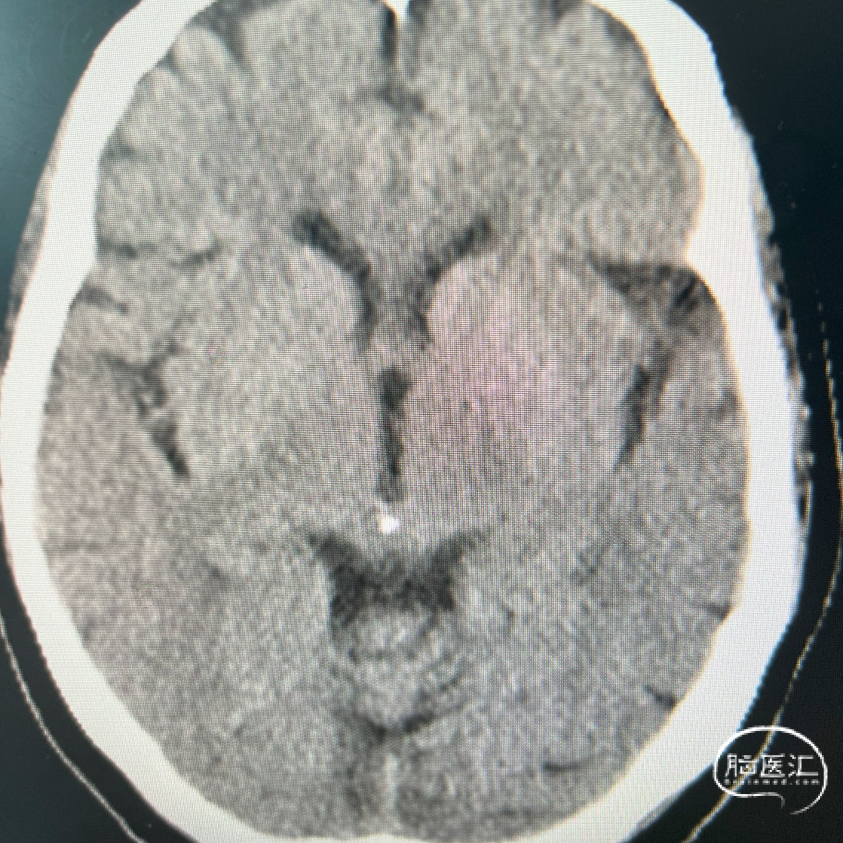

术前DSA影像:

右侧桡动脉穿刺置动脉鞘,泥鳅导丝配合6F 115cm Valent®颅内支撑导管内嵌行至右侧锁骨下动脉近右侧椎动脉起始段处,将导丝配合中间导管上行至椎动脉V3段,撤出泥鳅导丝,手推造影,显示:基底动脉中段可见重度狭窄,狭窄率约80%。

将微导丝头端置右侧大脑后动脉,沿微导丝引入2.0*10mm球囊,小心扩张狭窄段,撤出球囊后造影,原有狭窄较前稍好转,沿微导丝引入支架用微导管置于基底动脉,撤出微导丝,保留微导管,沿微导管引入3.5*15mm Neuroform EZ支架,缓慢释放,复查造影,狭窄较前明显好转,支架贴壁良好。

复查Dyna CT,颅内未见出血及造影剂外渗。